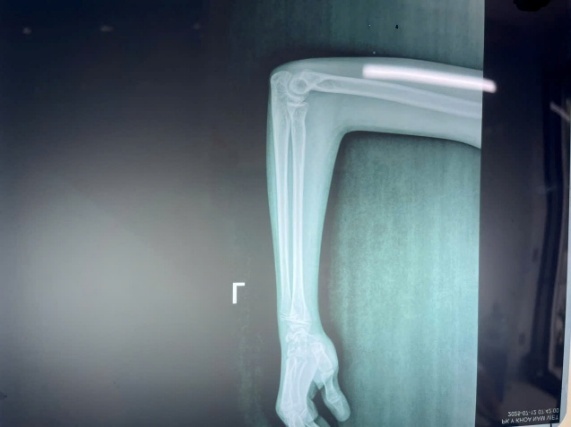

Postoperative check radiographs showed the radial head restored to anatomic position with a stable humeroradial joint (Figure 3). The postoperative course was stable; swelling was mild and pain was moderate, controlled with simple analgesics. The Kirschner wire was removed at 3 weeks without infection or displacement, and the long-arm plaster splint was removed at 6 weeks, at which time the child began supervised active exercises with a rehabilitation specialist.

At 1 year of scheduled follow-up, the patient had resumed nearly all normal activities, including self-care and non-contact sports, with only a 10° terminal limitation of forearm pronation compared with the uninjured side. There was no recurrent dislocation, chronic pain, elbow deformity, or nerve palsy. Radiographs showed an anatomically aligned radiocapitellar line, confirming the success of annular ligament reconstruction.